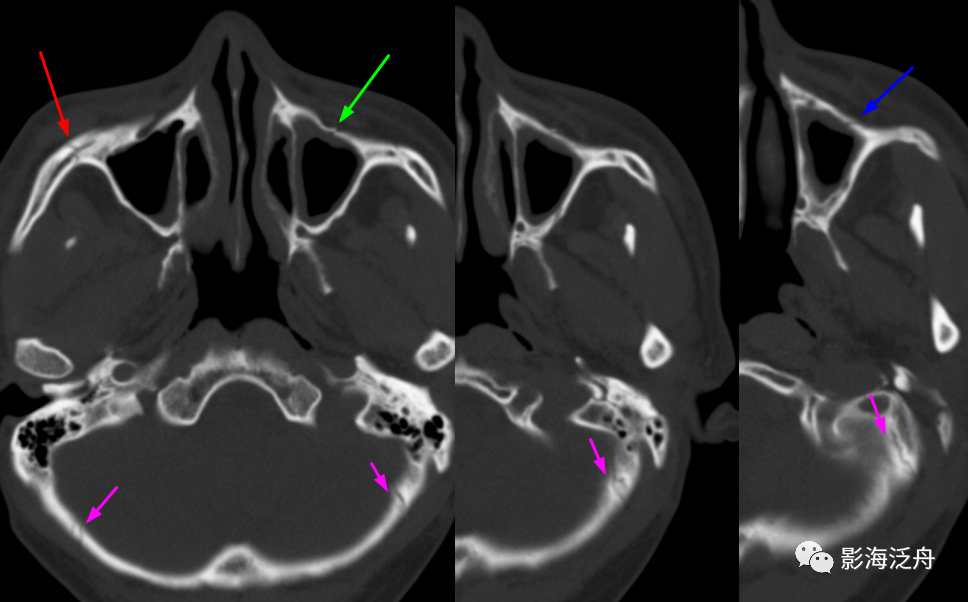

【病例讨论】鼻骨,上颌窦骨壁骨折! [病例帖]

连续层面的第三层左侧上颌窦前壁又显示一透亮线影(蓝箭),这个是骨折